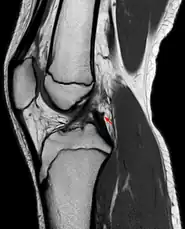

- Posterior meniscofemoral ligament on MRI, sagittal

- Posterior meniscofemoral ligament (Wrisberg) behind the posterior horn of the lateral meniscus close to its insertion. Sometimes wrongly interpreted as a meniscal tear.